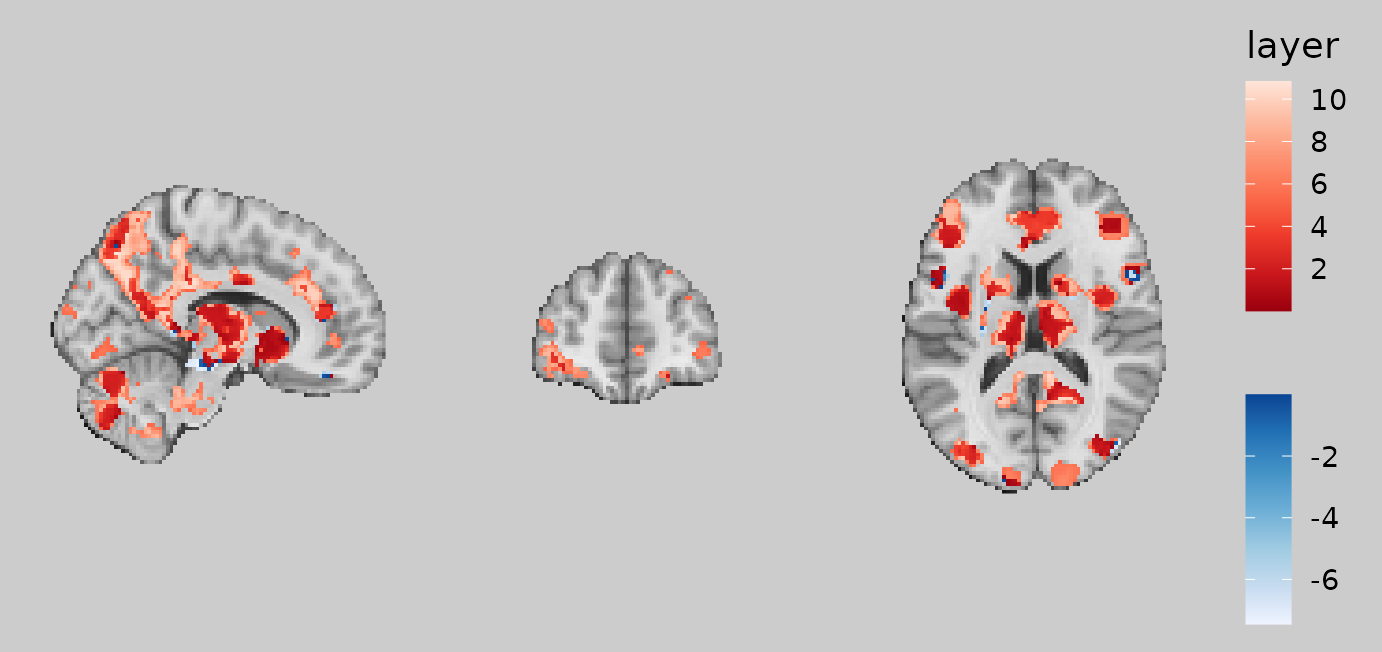

# define a reusable object that has the same images and slices

gg_base <- ggbrain(bg_color = "gray80", text_color = "black") +

images(c(underlay = underlay_2mm, overlay = echange_overlay_2mm)) +

slices(c("x = 10", "y = 50", "z = 15"))

gg_obj <- gg_base +

geom_brain(definition = "underlay", fill_scale = scale_fill_gradient(low = "grey8", high = "grey62"), show_legend = FALSE) +

geom_brain(definition = "overlay", fill_scale = scale_fill_bisided(), show_legend = TRUE)Now that we have geom_* layers in our

ggbrain object, we can finally plot our figure to see the

result.

plot(gg_obj)